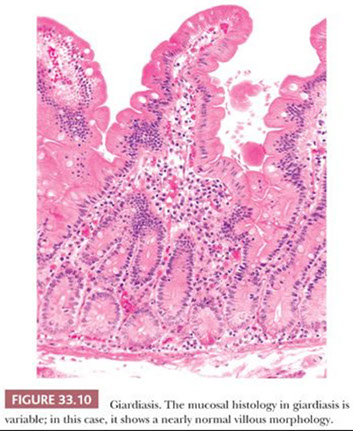

Giardia duodenalis

Giradia lamblia

aka G duodenalis or G intestinalis; described by Leeuwenhoek looking at his own poop; flagellated only need 10 cysts to infect; resistant to chlorine, thus endemic in unfiltered water

- pear-shaped, c 2 equal size nuclei, do not invade and sm bowel morphology may be normal, though can have inflam c heavy infx

Giardia trophozoites on mucosal surface